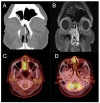

Inverted papillomas (IP) are the most common sinonasal tumor with a tendency for recurrence, potential attachment to the orbit and skull base, and risk of malignant degeneration into squamous cell carcinoma (SCC). While the overall rate of recurrence has decreased with the widespread adoption of high-definition endoscopic optics and advanced surgical tools, there remain challenges in managing tumors that are multiply recurrent or involve vital neurovascular structures. Here, we review the state-of-the-art diagnostic tools for IP and IP-degenerated SCC, contemporary surgical management, and propose a surveillance protocol.